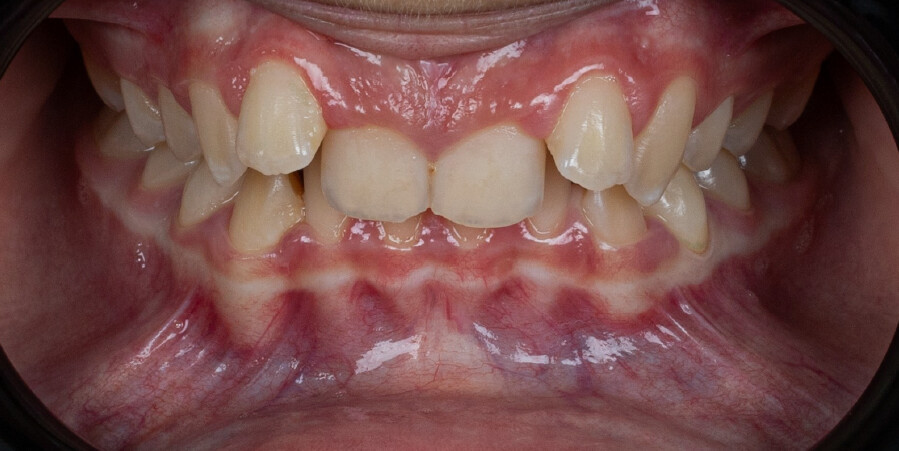

A 13-year-old male patient presented with a deep bite, characterized by near-complete coverage of the mandibular incisors. Clinical evaluation revealed bi-arch crowding, dental rotations, and proclination of the maxillary lateral incisors, contributing to the patient’s esthetic concerns. The facial profile was retrusive, consistent with mandibular retrognathism, and no significant periodontal abnormalities were detected.

The patient presented with a skeletal Class II relationship with bilateral molar and canine Class II and a Class II division 2 dental pattern. The deep bite was associated with anteroinferior crowding and an accentuated Curve of Spee. Facial analysis revealed good symmetry, a slightly increased lower facial third, and a convex profile characterized by mandibular and chin retrusion. Lip competence was mildly reduced, with a decreased nasolabial angle and mentalis hyperactivity, all of which compromised overall facial harmony.